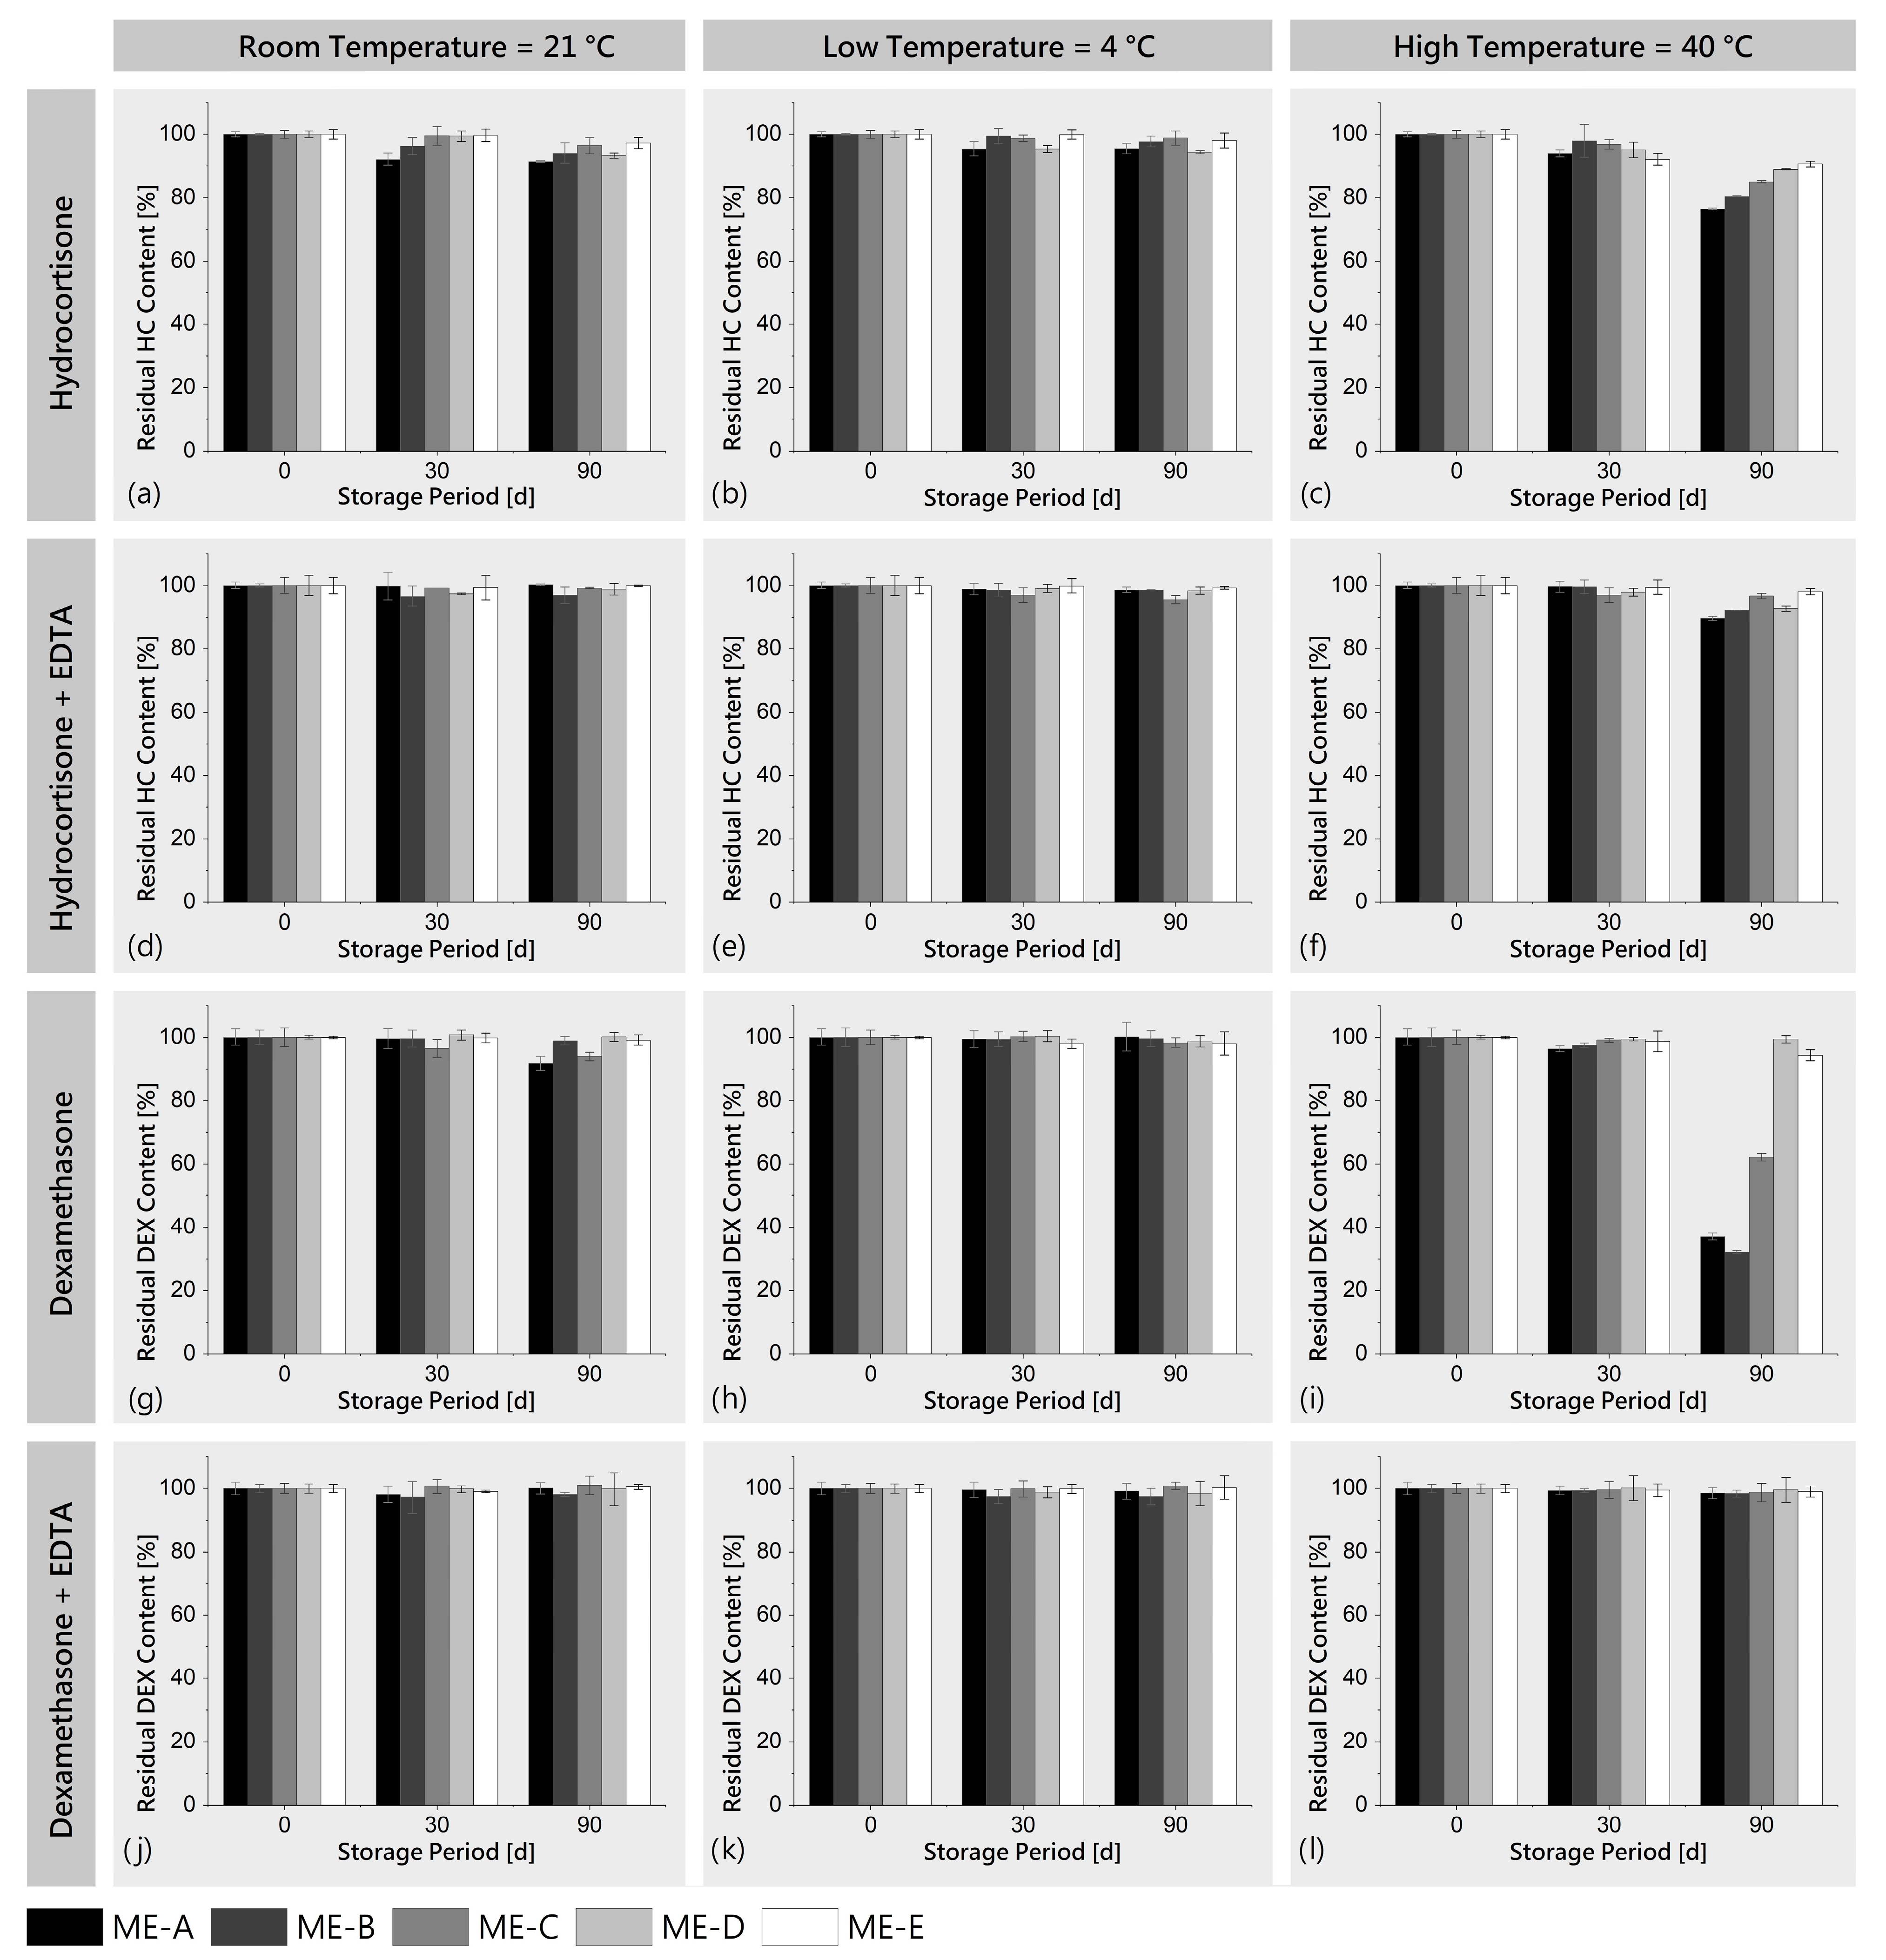

3.2.1. Storage Stability

3.2.2. Sterilization Stability